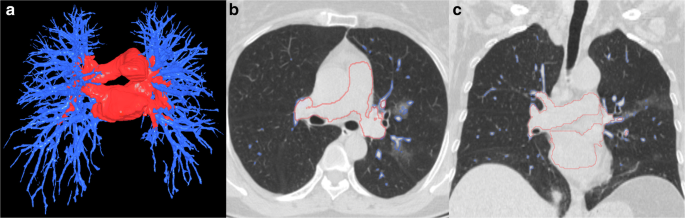

Fig. 3

figure 3

Example of intrapulmonary and extrapulmonary vessel segmentation using the U-Net framework. a 3D visualization of the segmentation vessels, and (b, c) the segmentation contours of the vessels overlaid on the original CT images